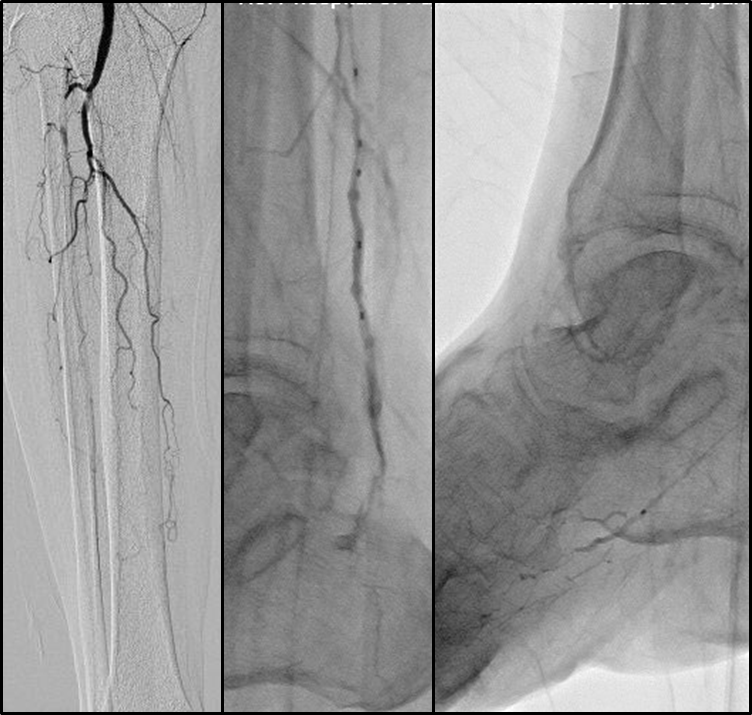

针对BTK病变,可采用多种腔内技术:

逆行技术

Trans-luminal

From no-target artery

Through pedal arch or ACA/PCA

To distal cap of CTO in target artery

Transcutaneous

Surgery exposure

Puncture

区域化操作策略:

平直区域:可快速通过(真腔或内膜下);

关键区域(如CTO开口、出口、BTA区域):必须谨慎操作,避免穿孔等并发症。